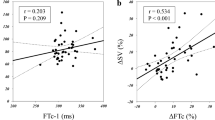

The percentage change in carotid corrected blood flow time was plotted on the x-axis, while the changes in SBP and MAP from baseline at 3 min after intubation were plotted on the y-axis to create a scatter trend plot (Fig. 6). Pearson correlation analysis was employed to examine the relationship between ΔFTc and ΔSBP, ΔDBP, and ΔMAP at 3 min after intubation. The results revealed a negative correlation between ΔFTc and both ΔSBP and ΔMAP, but no significant correlation with ΔDBP. The correlation coefficient for ΔFTc and ΔSBP was r = -0.30 (p = 0.02), with a linear regression equation of Y = 16.73–0.73X. Similarly, the correlation coefficient for ΔFTc and ΔMAP was r = -0.20 (p = 0.04), with a linear regression equation of Y = 11.10–0.40X. Due to some patients experiencing postintubation hypertension at 3 min after intubation, vasoactive drugs or rehydration were promptly administered, which may have influenced subsequent blood pressure values; therefore, only the correlation analysis between ΔFTc and ΔSBP, ΔDBP, and ΔMAP at 3 min was conducted.